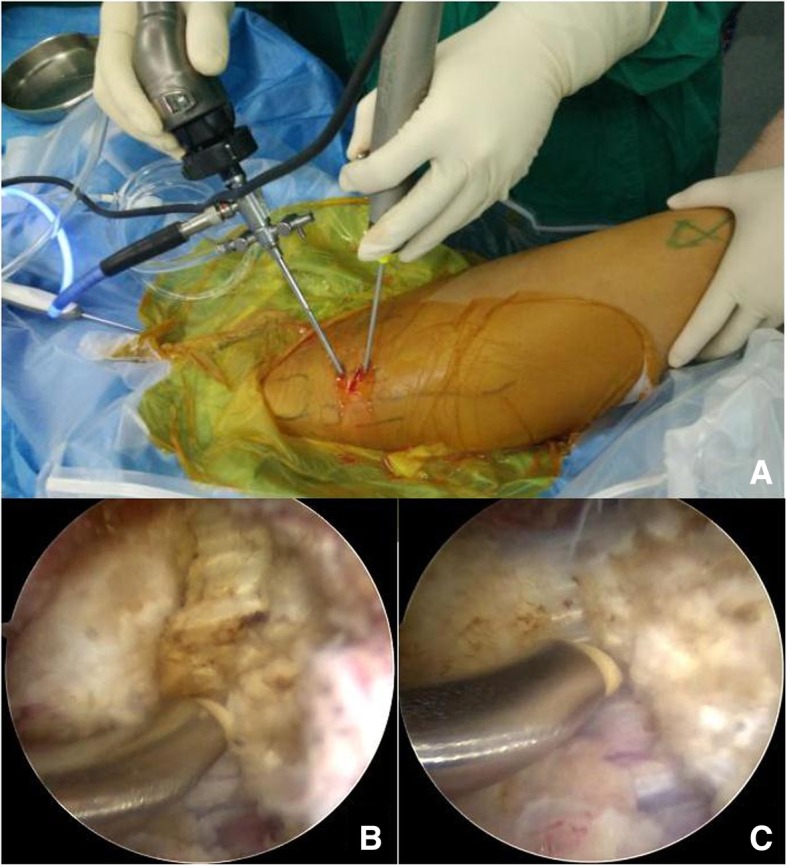

Before the operation, body surface symbols and surgical incisions were marked (Fig. 3). A 70 degrees arthroscope (Arthrex Inc., Naples, Florida) with a diameter of 2.7 mm was used to visualize tissue via the proximal portal. RFA was performed through the distal approach and contracture band was divided by during arthroscopic procedure while the patient was under subarachnoid anesthesia in the right side-lying position with rigid buttocks fixation. This position facilitated the assessment of surgical effects during the operation by comparing the degree of knee flexion when the hip extended with that before the procedure. In the arthroscopic images, a thick contracture tract was discernible while the surrounding fibrous connective tissue was debrided by mechanical gouging system (Arthrex Inc., Naples, Florida) (Fig. 4a). Then a plasma knife was used to cut off the tract from the outside edge to the inside gradually (Fig. 4b & c). After complete transection, the passive knee flexion could easily reach 120°. Thorough debridement and hemostasis around the broken ends were conducted with the radiofrequency ablation.

Fig. 4.

Gross appearance (a) and arthroscopic images (b & c) during the operation. Contracture band was divided by the ablation electrode gradually